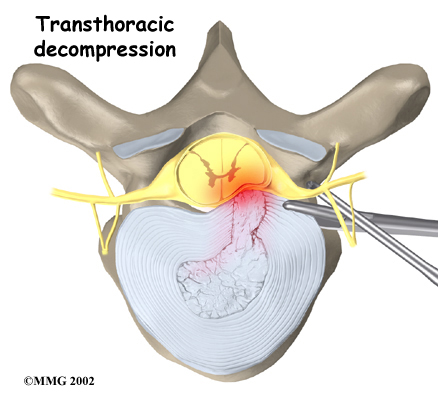

Transthoracic Decompression

Transthoracic describes the approach used by the surgeon. Trans means across or through. The thoracic region is the chest. So in , the surgeon operates through the chest cavity to reach the injured disc. This approach gives the surgeon a clear view of the disc.

With the patient on his or her side, the surgeon cuts a small opening through the ribs on the side of the thorax (the chest). Instruments are placed through the opening, and the herniated part of the disc is taken out. This takes pressure off the spinal cord (decompression).